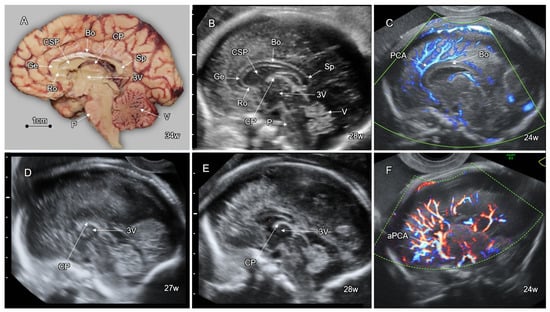

5. Disorders of the Corpus Callosum (DCC)

- Leombroni, M.; Khalil, A. Fetal midline anomalies: Diagnosis and counselling Part 1: Corpus callosum anomalies. Eur. J. Paediatr. Neurol. 2018, 22, 951–962. [Google Scholar] [CrossRef]

- Birnbaum, R.; Barzilay, R. The early pattern of human corpus callosum development: A transvaginal 3D neurosonographic study. Prenat. Diagn. 2020, 40, 1239–1245. [Google Scholar] [CrossRef]